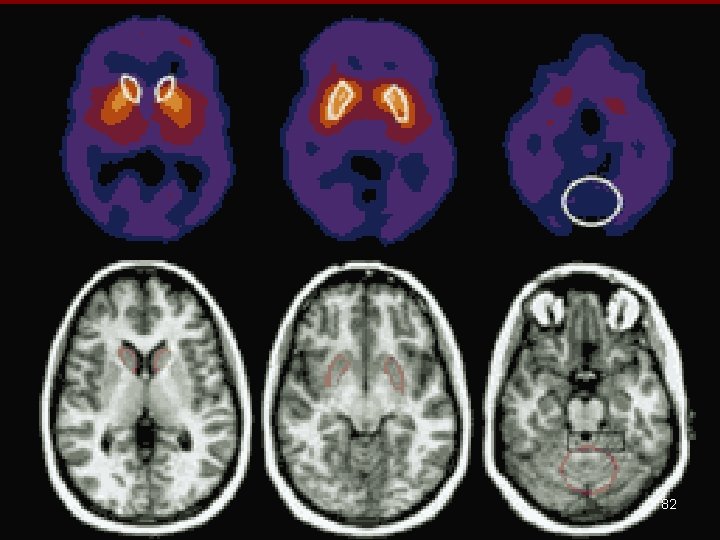

PET Scan & SPECT Scan • PET = Positron Emission Tomography • Single Photon Emission Computed Tomography 76

PET NUCLEAR MED + CT or MRI- co-registration 79

81

82